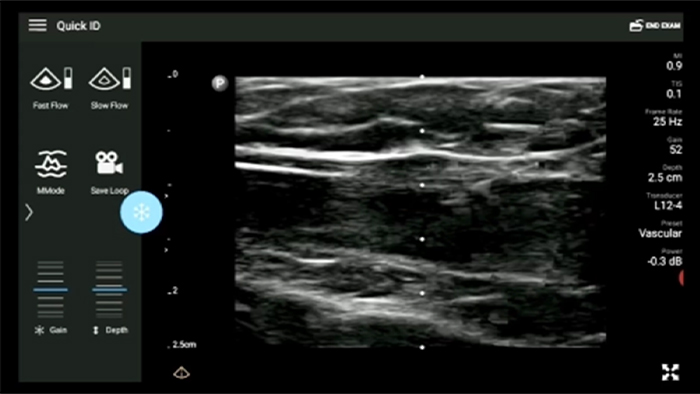

Przenośny system Lumify do stosowania w anestezjologii pomaga wyraźnie uwidocznić granice tkanek, otaczające je nerwy, naczynia oraz powierzchnie powięzi podczas wprowadzania igły.

System Lumify pomaga wyraźnie zwizualizować wprowadzaną igłę, otaczające ją nerwy, naczynia oraz powierzchnie powięzi.